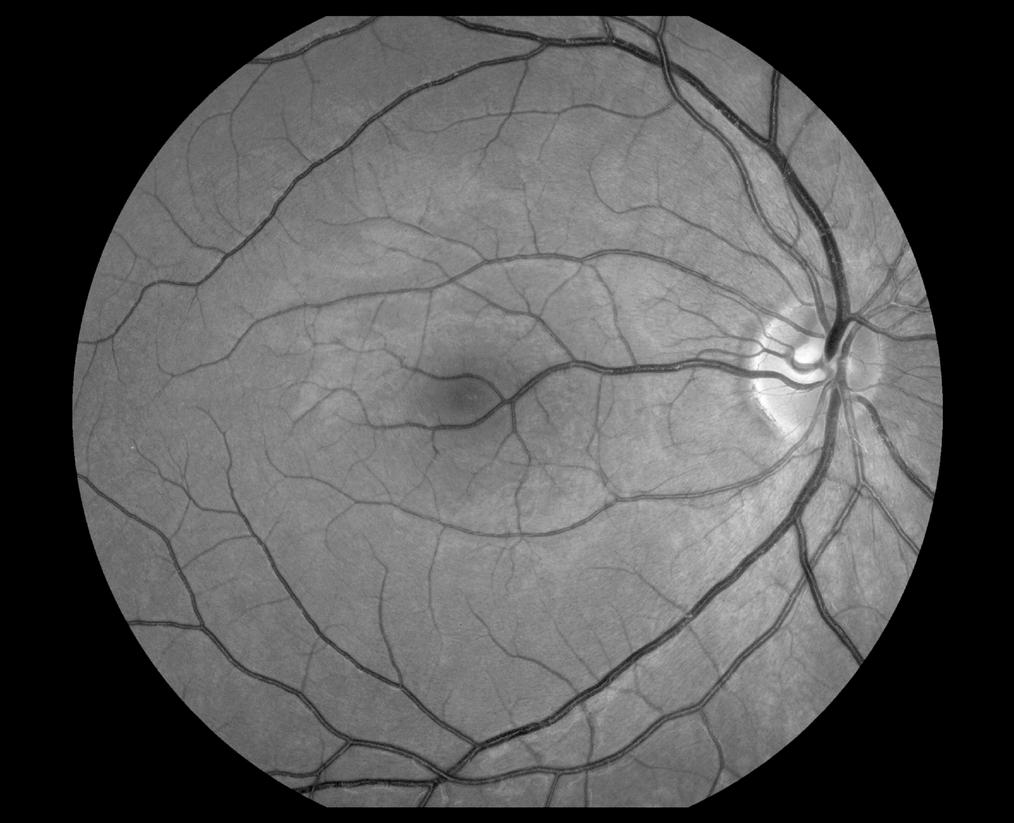

Congenital Retinal Macrovessel

Robert Mays, CRA, OCT-C

National Eye Institute

Bethesda, Maryland